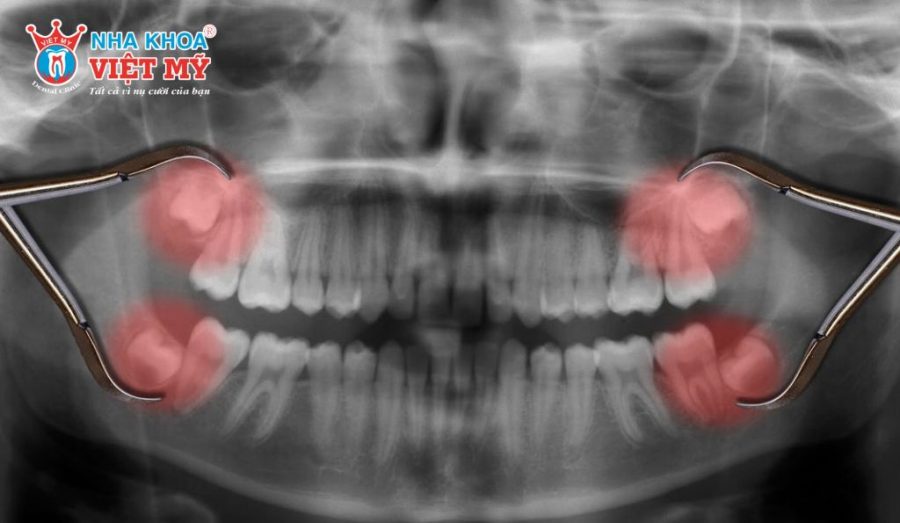

- Răng khôn mọc lệch, mọc ngầm gây đau nhức, sưng nướu hoặc đẩy các răng bên cạnh làm sai lệch khớp cắn.

Răng khôn mọc thẳng, chân răng đơn giản thường được nhổ dễ dàng, ít xâm lấn mô mềm và xương hàm nên vết thương sẽ hồi phục nhanh. Ngược lại, các trường hợp răng khôn mọc lệch, mọc ngầm hoặc có nhiều chân răng cong, gãy phức tạp sẽ khiến thủ thuật khó khăn hơn, đồng nghĩa với việc thời gian lành thương kéo dài.

Tổn thương dây thần kinh

Trong một số trường hợp răng khôn mọc ngầm sâu, chân răng nằm sát với dây thần kinh hàm dưới. Khi nhổ răng, có nguy cơ gây tê bì tạm thời ở môi, cằm hoặc lưỡi. Hiện tượng này thường chỉ kéo dài trong vài tuần và sẽ dần hồi phục, nhưng rất hiếm khi trở thành tổn thương vĩnh viễn.